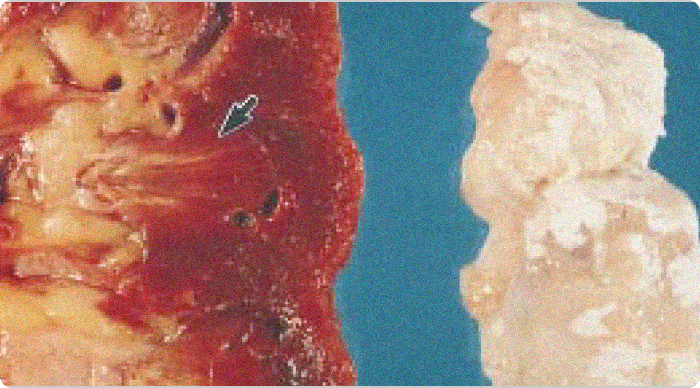

Images of gouty tophi in joint and kidney

Gouty tophi in joint and kidney. Chalky white urate deposits are visible in the articular cartilage (right). The corresponding kidney (left) shows yellowish areas in the pyramids (arrow) representing fibrosis and urate deposits.1

Adapted from Nickeleit V, et al. Nephrol Dial Transplant. 1997;12:1832-1838.

KRYSTEXXA has not been studied to reverse damage to the kidneys or any of the body's organs.

High power view of a tophus

High-power view of a tophus, with central urate deposition surrounded by mononuclear inflammatory cells and scattered giant cells.1

Side by side gouty tophi images

Gouty tophus in renal medulla (left; acid fuchsin – orange G stain, x125 original magnification). Center of a tophus with uric acid crystals (right; polarized light; x140 original magnification).1